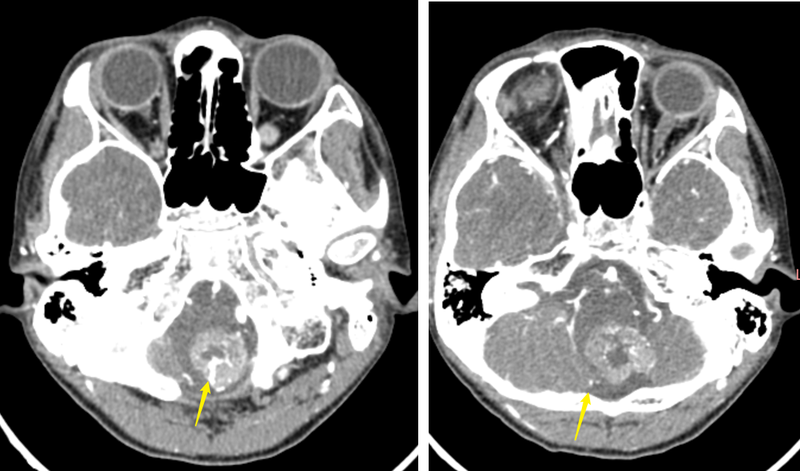

腦干腫瘤,竟然是罕見的神經(jīng)鞘瘤!

9歲的男孩小明(化名),經(jīng)常早上起來嘔吐,伴有咳嗽、咳痰,看了許久也不見好轉(zhuǎn)。醫(yī)生建議查個頭顱CT,不查不要緊,一查嚇一跳,發(fā)現(xiàn)腦干上長了個東西。于是連忙安排檢查頭顱磁共振發(fā)現(xiàn)腦干的延髓段真的有一個巨大的腫瘤。眾所周知,腦干是人腦的中樞,而延髓是又腦干最核心的部分,體積不大,但關(guān)系到運動、心跳、呼吸等多種生命最重要的作用。是真正意義上的生命中樞。腫瘤不偏不倚正好在延髓,使其明顯受壓。但患者目前除了有咳痰增加外,幾乎沒什么癥狀,而且四肢手腳活動完全正常,吞咽、咳痰等功能也正常。因此手術(shù)切除腫瘤具有極大的風(fēng)險,稍有不慎,便會引起癱瘓,甚至影響吞咽、咳嗽以及呼吸功能,后果不堪設(shè)想。多方打聽,咨詢了全國很多大醫(yī)院的專家,有的說是室管膜瘤,還有的說是實質(zhì)性血管母細(xì)胞瘤等等。但都說手術(shù)風(fēng)險極大,有可能無法全切腫瘤并導(dǎo)致癱瘓或者咳痰、呼吸功能障礙。手術(shù),目前患者沒什么明顯的癥狀和異常,一旦出問題,后果不堪設(shè)想,家屬難以接受;不手術(shù),腫瘤很大了,可能遲早會引起癱瘓等嚴(yán)重的后果。家屬因此陷入極大的糾結(jié)之中。經(jīng)人介紹找到我們,仔細(xì)了解病情和影像后,詳細(xì)和家屬闡明了病變可能的性質(zhì)和手術(shù)的價值。征得家屬的理解,決定為小明進(jìn)行腦干腫瘤手術(shù)。通過仔細(xì)研究術(shù)前CT和磁共振,我們認(rèn)為室管膜瘤和血管母細(xì)胞瘤的可能性小,更像罕見的腦內(nèi)神經(jīng)鞘瘤。術(shù)前為患者進(jìn)行了詳盡的神經(jīng)功能評估,發(fā)現(xiàn)患者除了左下肢感覺誘發(fā)電位輕度異常外,四肢運動、感覺功能均正常,吞咽、咳嗽功能和喉鏡檢查均未發(fā)現(xiàn)異常。這也為手術(shù)帶了極大的挑戰(zhàn)。我們采取枕后正中入路,為患者進(jìn)行手術(shù),術(shù)中發(fā)現(xiàn)腫瘤位于腦干內(nèi),并向外生長。術(shù)中冰凍病理提示可見梭形細(xì)胞,神經(jīng)鞘瘤首先考慮。與典型的神經(jīng)鞘瘤不同的是,雖然腫瘤對起源于脊髓上的頸神經(jīng)根和后組顱神經(jīng)有包繞,但還是能夠通過顯微手術(shù)完全分離,并沒有發(fā)現(xiàn)腫瘤起源于上述神經(jīng)。同時,腫瘤與周邊顱底的硬腦膜完全沒有附著,因此也排除了腦膜瘤的可能性。通過精細(xì)手術(shù),我們徹底將腫瘤完全從腦干上分離下來,并保證了腦干的完整性。手術(shù)成功全切腫瘤。術(shù)后患者神經(jīng)功能完全保留,四肢活動良好。從住院到康復(fù)出院,僅僅8天時間。顱內(nèi)神經(jīng)鞘瘤大約占顱內(nèi)腫瘤的8%,大多數(shù)起源于第八對前庭神經(jīng),也就是常說的聽神經(jīng)瘤。真正起源于腦內(nèi)神經(jīng)鞘瘤不到顱內(nèi)神經(jīng)鞘瘤的1%。迄今為止,也僅僅只有70余例的臨床報道(實際可能會更多一些)。而腦干內(nèi)的神經(jīng)鞘瘤就更受之又少了。發(fā)生機(jī)制及其來源目前仍不是很清楚,可能是由血管周圍神經(jīng)叢的許旺氏細(xì)胞發(fā)生的,也可能是軟腦膜向許旺氏細(xì)胞的轉(zhuǎn)化引起的異位神經(jīng)鞘瘤??傊捎诓±∩?,這方面的研究不是很多。該病多兒童和年輕人,男性多見。而小明僅僅只有9歲,更是目前已知年齡最小的患者。對于腦干腫瘤,雖然手術(shù)難度高、風(fēng)險大,但也并非以往所認(rèn)為的手術(shù)禁區(qū)。我們經(jīng)過術(shù)前認(rèn)真評估、全面準(zhǔn)備,術(shù)中精細(xì)操作,加上新華醫(yī)院0到100歲全年齡段ICU團(tuán)隊專業(yè)的圍手術(shù)期處理,變不可能為可能,讓腦干腫瘤患者一樣可以得到非常滿意的結(jié)果。